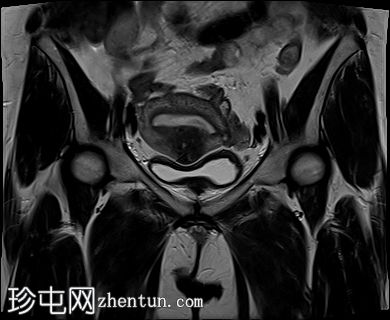

冠状位

T1加权像

2.jpg

增大的子宫腹股沟区(AVF)显示:

子宫前壁交界区局灶性增厚,边界不清。形成直径约3厘米的局灶性肿块样病变,轻度压迫膀胱。肿块边界模糊不清,可见多个细小出血灶,在T1加权像和T2加权像上均呈高信号,提示局灶性子宫腺肌症。

子宫体前壁可见另一处病灶,位于上述病灶尾侧,边界清晰(有包膜)。该病灶在T1和T2加权像上均呈低信号,内部未见异常信号灶,周围可见少量明显血管通道,提示为小型子宫肌瘤。

子宫内膜厚度正常。

宫颈MRI表现正常,可见少量纳博氏囊肿。

边界模糊不清是局灶性子宫腺肌症(无包膜)的特征。此外,病灶内存在多个微小的内部出血灶(异位腺体),且邻近增厚模糊的交界区,这些都是局灶性子宫腺肌症的诊断标准。

在上述病灶尾侧可见另一处具有不同影像学特征的病灶,该病灶边界清晰(有包膜),且信号均匀(无微小的内部出血灶),提示可能合并子宫肌瘤。